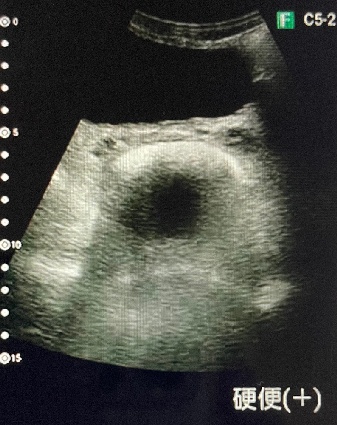

エコーを活用した看護を実践しています

↓画像をタップすると拡大します🔍